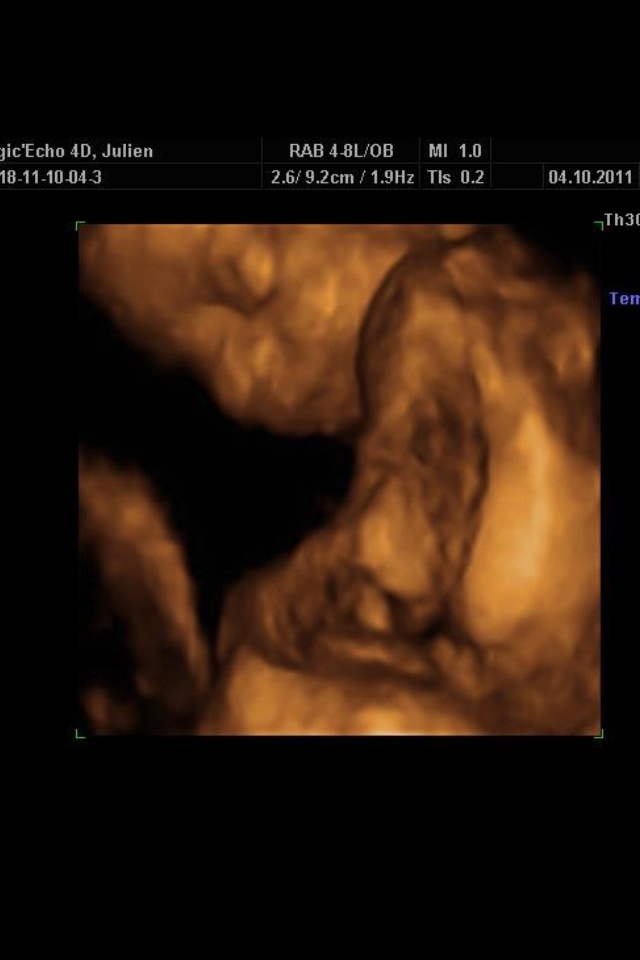

Quand je les avaient contacté ils mon dit c'est la bonne période bebe est pas trop gros

J'avais fait pareil pour Julien j'étais a 22 sa aussi